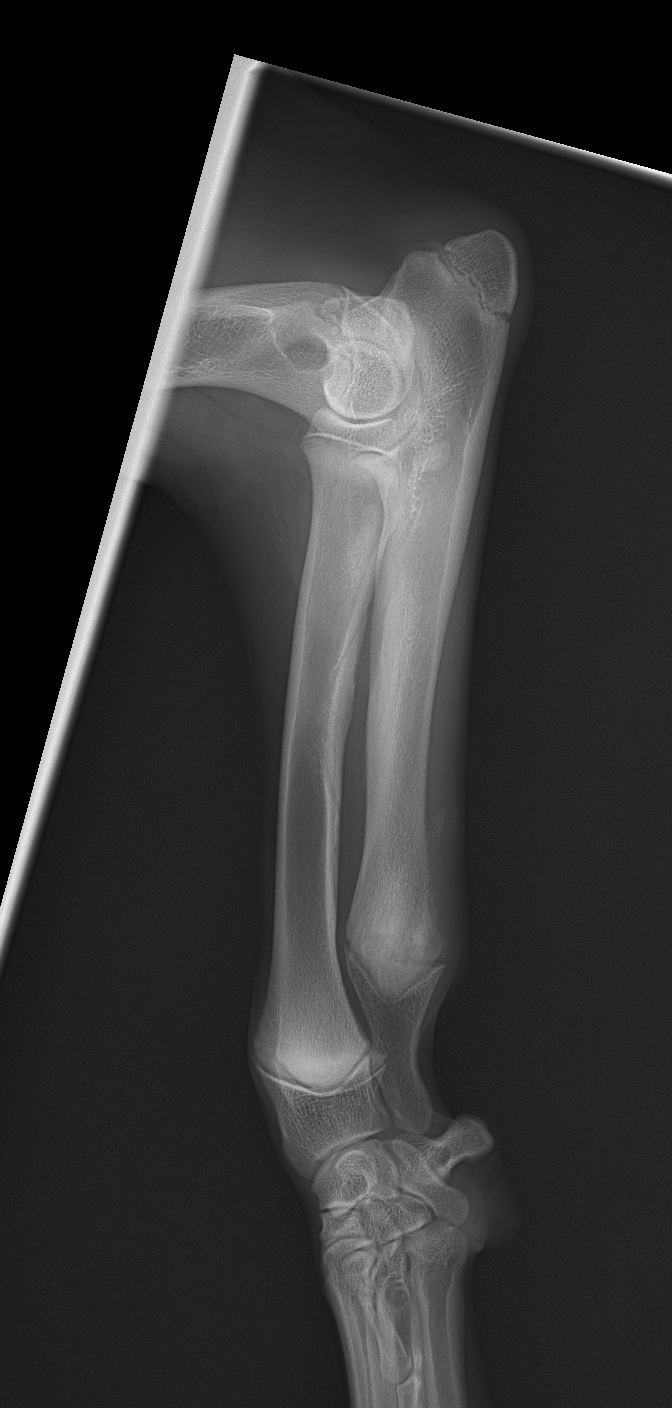

遠位尺骨部分切除術 大型犬のパピー(5mo)の前腕変形に対して、尺骨遠位骨部分切除術を実施。橈骨の成長が終了するまで待ってから変形による有痛症状があれば関節鏡による探査と橈骨の変形矯正を検討します。 症例カテゴリー 放射線治療整形外科軟部組織外科脳神経外科内科腫瘍外科救急・集中治療リハビリテーション科腫瘍内科内視鏡科脳神経科呼吸器外科中医・漢方猫の腎移植循環器科